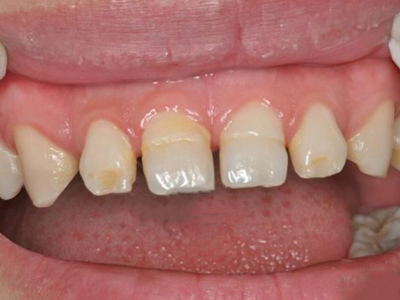

牙釉质发育不全牙齿白斑图

牙釉质发育不全患者可以仅仅出现牙齿色泽和透明度的改变,形成白垩色釉质,即类似于牙齿上有白斑,此时牙冠形态通常较完整。

牙釉质发育不全牙齿上出现白色的斑块图

牙釉质发育不全患者牙釉质表面出现白垩色釉质,表现为牙齿表面色泽不均匀,一般无自觉症状,并且此时牙冠形态较为完整,顶端出现小的缺损。

牙釉质发育不全牙齿变薄图

牙釉质发育不全患者的牙齿有色泽和透明度改变,表面出现白垩色釉质,同时牙齿顶端变透明、变薄,但患者可能无敏感、疼痛等自觉症状。

牙釉质发育不全牙齿表面有白色斑块图

牙釉质发育不全患者病情较轻时,只出现色泽、透明度改变,牙齿表面出现不规则的白色斑块,透光度降低,但牙齿形态较完整,无明显缺损。

牙釉质发育不全牙齿有白斑图

牙釉质发育不全病情较轻时,会导致牙齿色泽和透明度改变,形成白垩色釉质,表现为牙齿不规则白斑,此时牙冠形态比较完整,患者无其他不适症状。

牙釉质发育不全牙上发白图

轻度的牙釉质发育不全患者,牙齿出现色泽和透明度的改变,此时不会影响牙齿的完整形态,也不会导致疼痛不适,仅表现为牙齿上有白色斑点、牙列不齐。

牙釉质发育不全牙齿上有白点图

牙釉质发育不全病情较轻者,只表现为牙齿上有白点,形状不规则,造成牙齿的透明度下降,但牙齿形态依旧完整,也不影响进食。

牙釉质发育不全患者牙齿上出现不规则形状的白色斑块,无牙齿的缺损,但可存在牙龈肿胀、出血的表现。